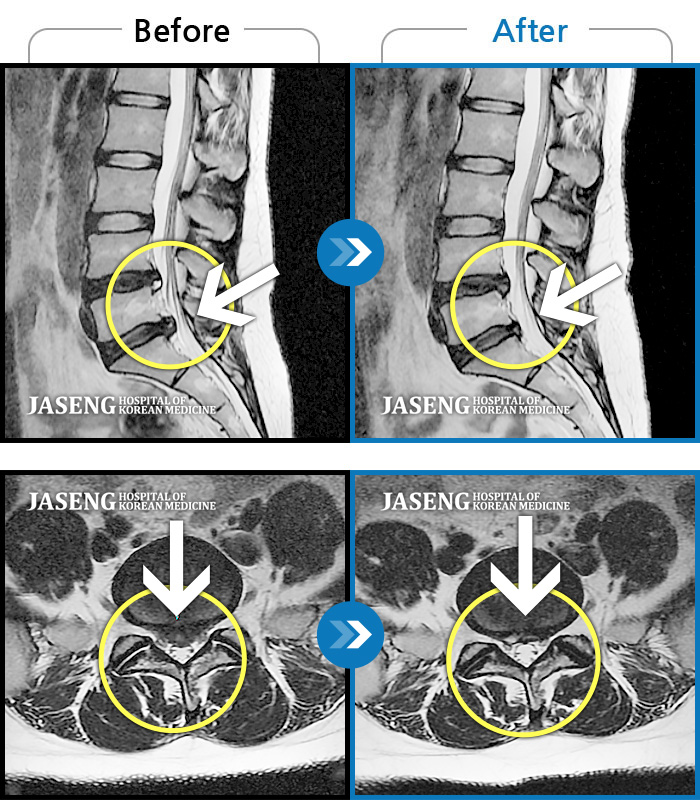

허리디스크

보라매 · 왕오호 원장

허리와 좌측 엉치 통증

촬영시기

2015.12.29 ~ 2018.10.11